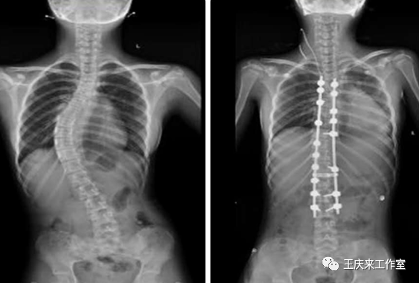

(3)重度:cobb角>45°,病情进展迅速者可能就要考虑手术矫正治疗。